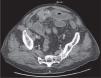

The patient was treated conservatively as a possible partial obstruction secondary to adhesions. However, he continued to vomit and developed a high temperature and abdominal distension. Repeat CT scan demonstrated a 3 cm, mixed attenuation intra-luminal lesion within the distal small bowel suggestive of a gallstone (Figure 1).

Figure 1.

CT image showing ectopic gallstone in the small bowel.